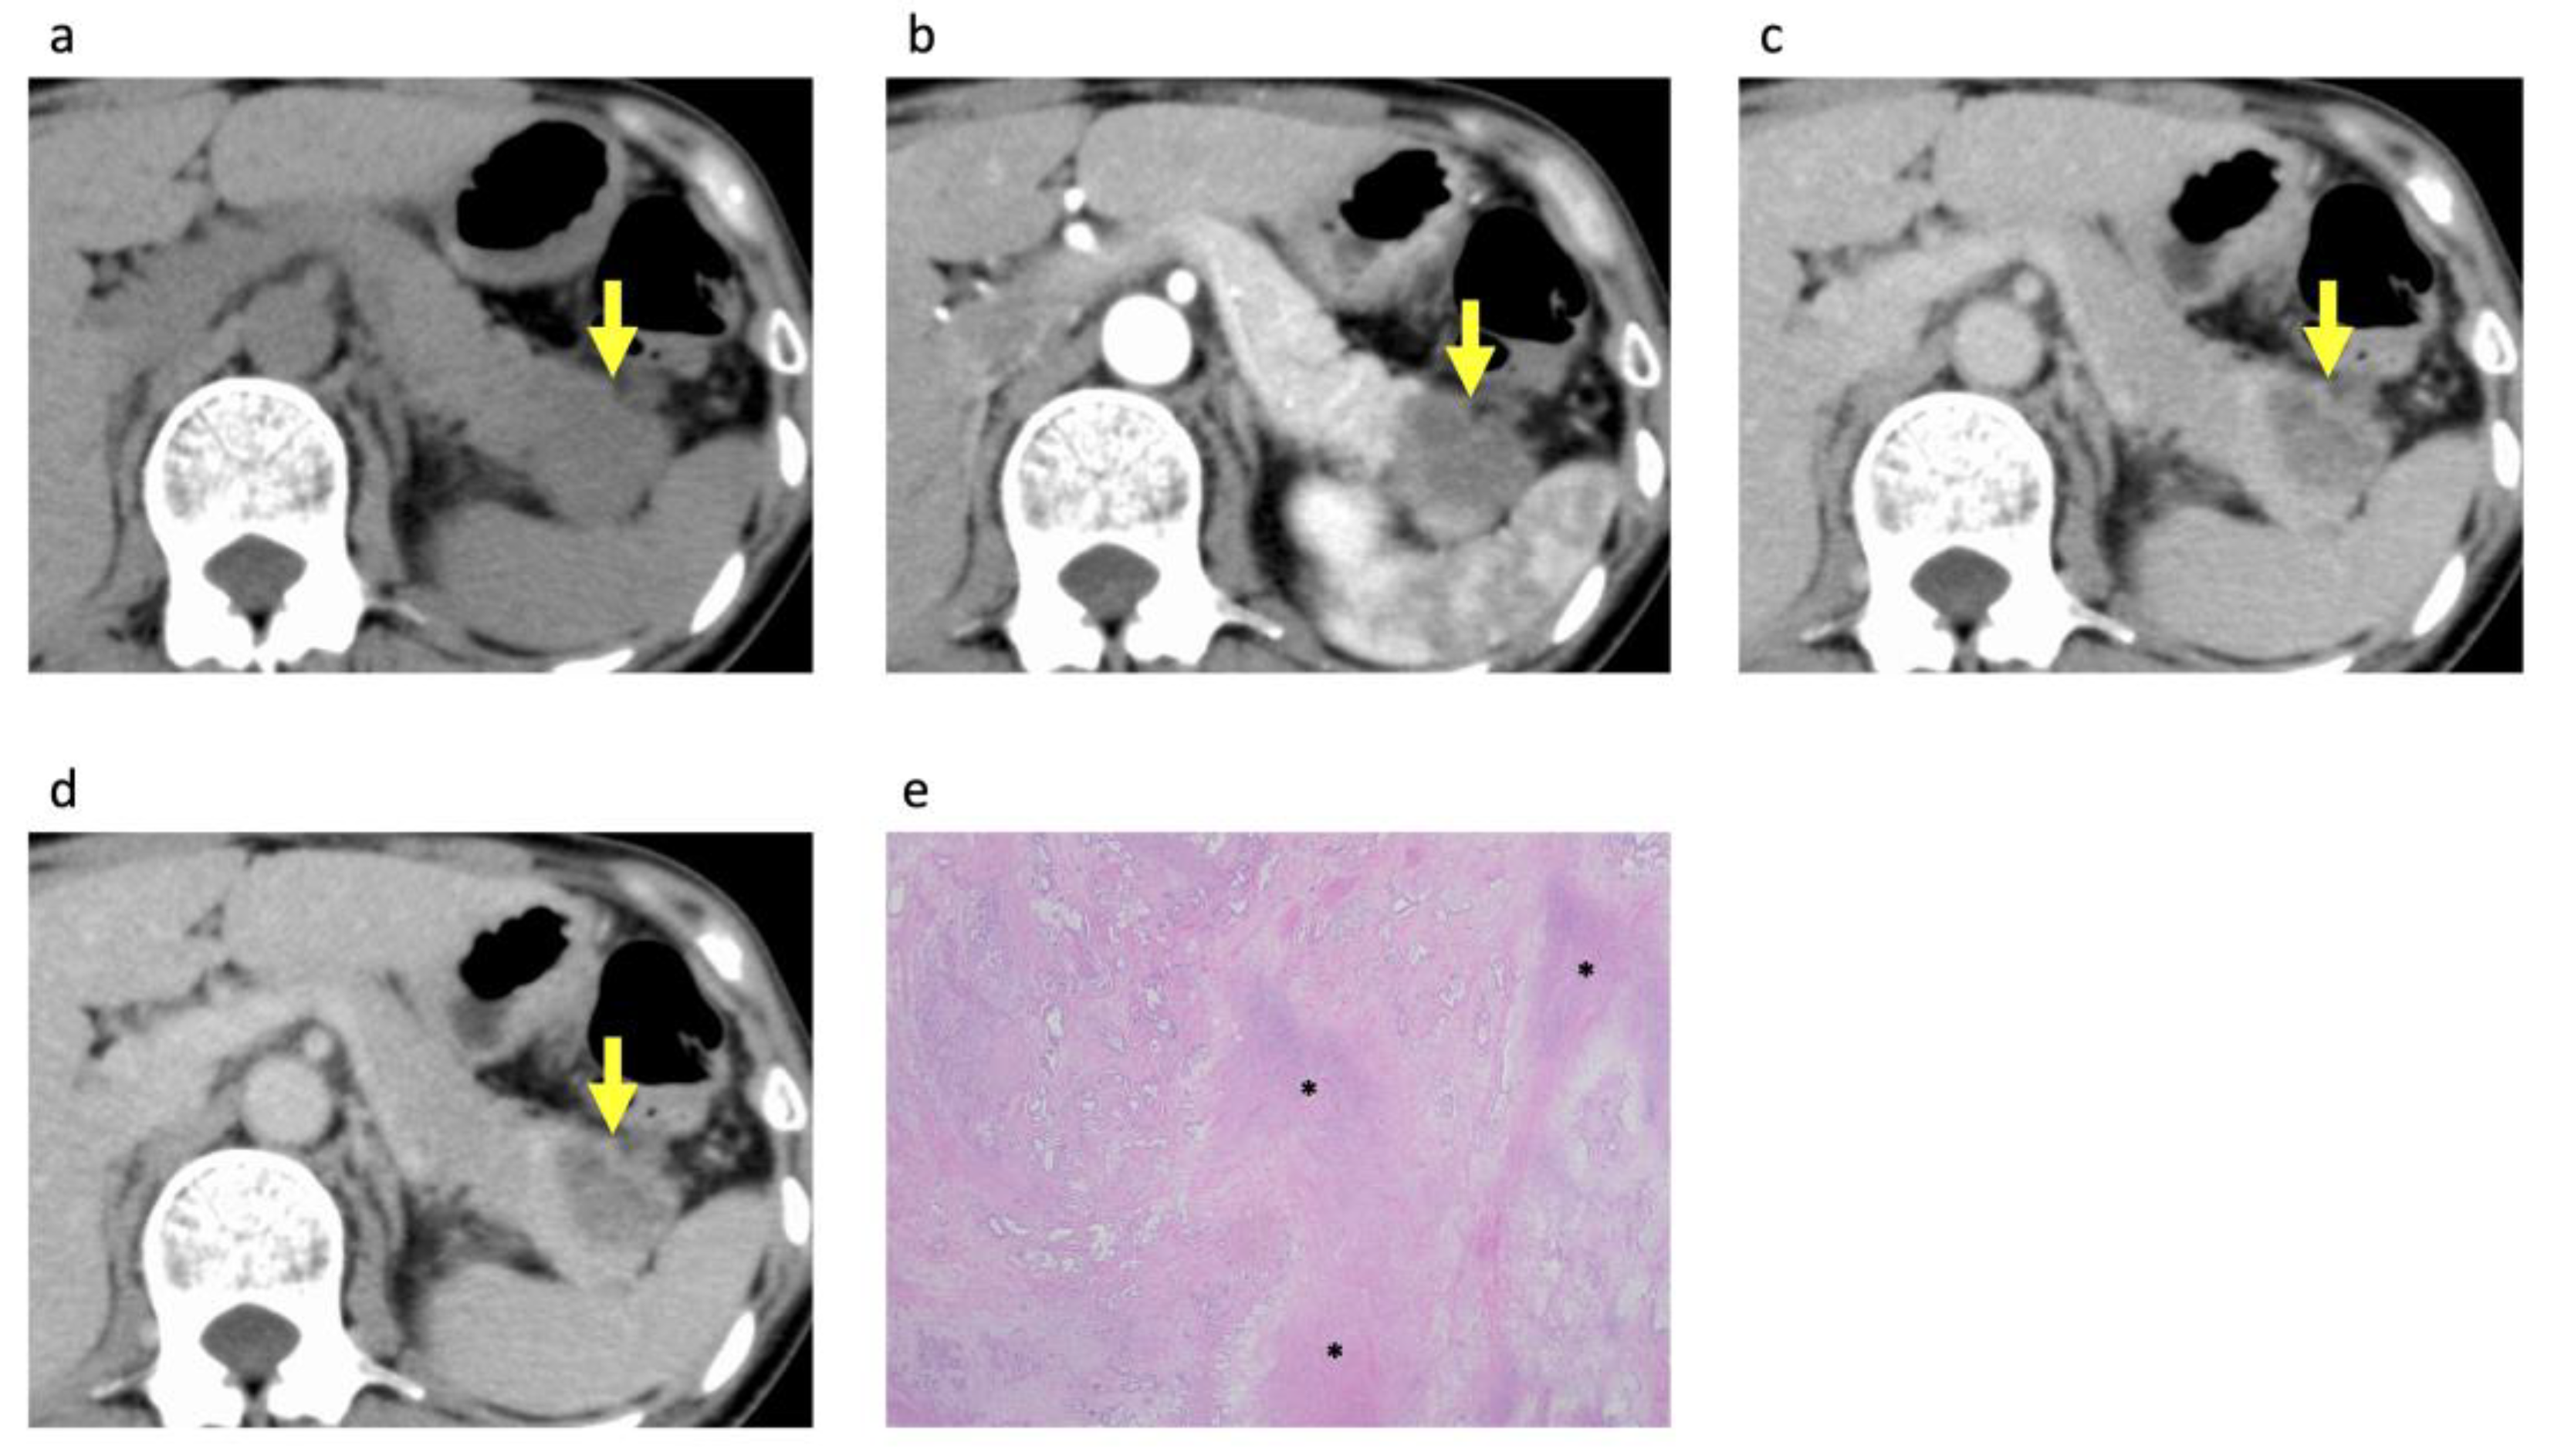

3.3. Histopathological Analysis of the PDACs According to Rim Enhancement